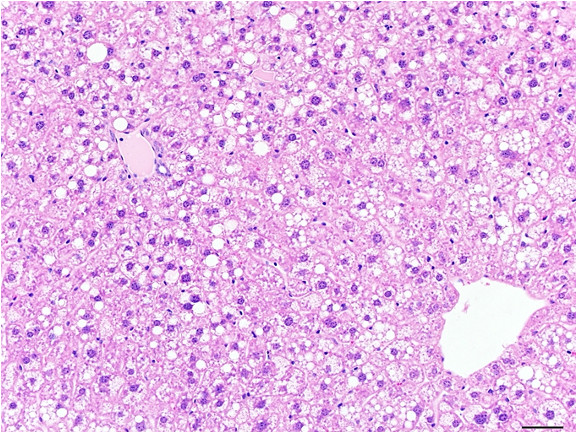

Figure 6: Histopathology for C57BL/6NTac mice placed on D09100310 diet (MASH B6NTac) or kept on chow diet (Control B6NTac) from 6 weeks of age. Animals were on diet for 27, 35 or 53 weeks. Hematoxylin and eosin (H&E) staining illustrates morphological changes including steatosis and infiltration of immune cells. Activated HSCs were identified in liver sections by using a rabbit polyclonal antibody to alpha-smooth muscle actin (a-SMA) (1:500 dilution; ab5694; Abcam, Cambridge, MA) which was detected by an anti-rabbit IgG embedded polymer with embedded horseradish peroxidase and visualized with 3,3′-diaminobenzidine (DAB) chromogen (Agilent, Carpentaria, CA). Hepatocellular lipid droplets were identified by visualization of the lipid-binding protein adipophilin known to be expressed in steatotic livers. Sections of livers were probed using a rabbit polyclonal anti-adipophilin antibody (1:200 dilution; NB110-40877, Novus Biologics, Littleton, CO) which was detected by an anti-rabbit IgG embedded polymer with embedded horseradish peroxidase and visualized with 3,3′-diaminobenzidine (DAB) chromogen (Aligent, Carpentaria, CA). Picrosirius red (PSR) staining illustrates collagen I and III fibers and is used to measure fibrosis. The same individual MASH or control animal is shown for all four stains in a particular time point. Different individual animals were used for each time point (i.e. data is not longitudinal by animal). Histopathology services provided by IDEXX BioAnalytics.